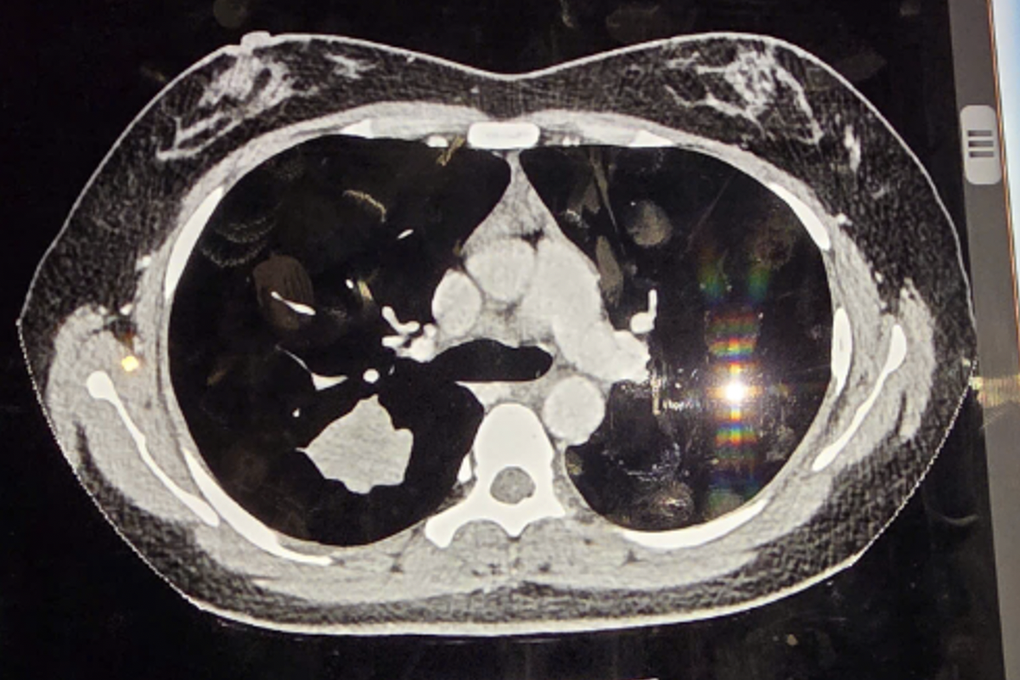

Nhưng trong lần khám định kỳ năm nay, kết quả chụp CT ngực liều thấp khiến cô gái và gia đình như chết lặng, khi bác sĩ thông báo đã phát hiện một khối u trong phổi, có nguy cơ ung thư.

Ảnh chụp CT ghi nhận khối u phổi của cô gái (Ảnh: BVCC).

Ngay lập tức, ca phẫu thuật nội soi lồng ngực được chỉ định. Ê-kíp phẫu thuật gồm PGS.TS.BS Vũ Hữu Vĩnh, BS.CKI Phạm Phú Khang phối hợp cùng đội ngũ Gây mê hồi sức đã tiến hành thăm dò, phát hiện khối u tại phân thùy S2 kích thước 4x3cm, rắn chắc và co kéo nhu mô phổi.